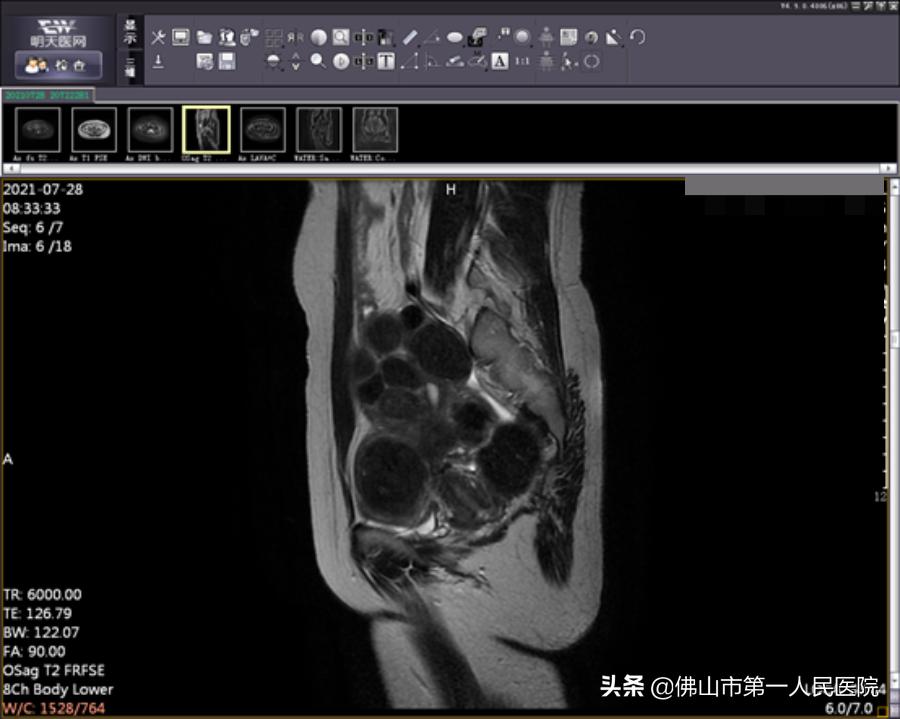

术后图像(海扶使肿瘤组织发生凝固性坏死)

海扶刀手术时长2小时50分钟,治疗时间25分钟。王女士表示术中无明显不适,术后数小时后就能下床正常活动。术后复查磁共振提示消融效果满意,术后月经量正常,术后复查MRI肌瘤消融满意。